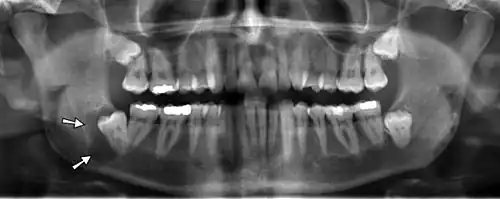

Panoramic radiographs have the capability to demonstrate a portion of the neck and display atheromas (calcifications in the carotid artery) which are an indication of both local and generalized (systemic) atherosclerosis. Atherosclerosis of the coronary arteries leading to myocardial infarction (heart attack), and atherosclerosis of the carotid artery leading to stroke are the number one and number three most common causes of death in the United States.[6]

There is interest to look at panoramic radiographs as a screening tool, however further data is needed with regards if it is able to make a meaningful difference in outcomes.[7]

Additional research projects have further determined the prevalence rate of these atheromas in the general population (3–5%)[8][9] and among high-risk groups (over 25% in: recent stroke victims,[10] individuals with obstructive sleep apnea syndrome,[11][12][13] postmenopausal women,[14] type 2 diabetics,[15][13][16] individuals with dilated cardiomyopathy,[17][13] and among individuals who have received radiotherapy directed at the neck,[18][19]). These findings have been corroborated by other several other researchers.[20][21][22][23][13]

Atherosclerosis is attributed to risk factors that include cigarette smoking, hyperlipidemia, obesity, diabetes mellitus, and hypertension (high blood pressure). These factors, however, do not fully account for the risk of disease. Atherosclerosis has been conceptualized as a chronic inflammatory response to endothelial cell injury[24] and dysfunction possibly arising from chronic dental infection. In 2010, using the previously validated Mattila panoramic radiographic index to quantify the totality of dental infection (i.e., periapical and furcal lesions, pericoronitis sites, carious tooth roots, teeth with pulpal caries, and vertical bony defects), Friedlander's group determined that individuals with carotid artery atheromas on their panoramic radiographs had significantly greater amounts of dental infection/inflammation than atherogenic risk-matched controls devoid of radiographic atheromas.[25][26] While the Mattila index had been previously used to relate the extent of dental infection to coronary artery disease, this research is the first to link the full range of dental disease that it measures to panoramic radiographs evidencing calcified carotid artery atherosclerosis.